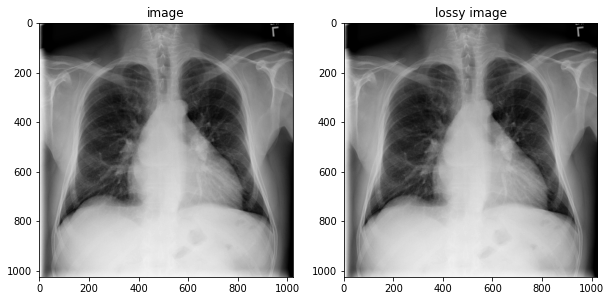

DICOM? 야 너두 할 수 있어